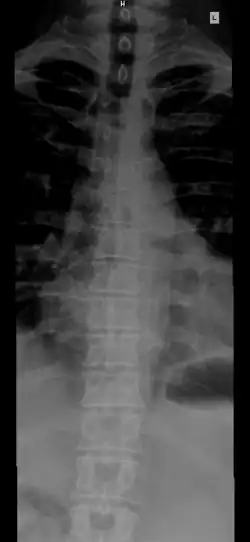

A thoracic spine X-ray of a 57-year-old male.

The thoracic curve, concave forward, begins at the middle of the second and ends at the middle of the twelfth thoracic vertebra. Its most prominent point behind corresponds to the spinous process of the seventh thoracic vertebra. This curve is known as a kyphotic curve.